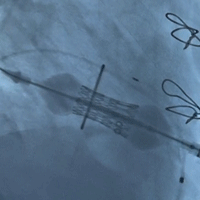

左室术后造影

(位置完美、无反流)

术前经详尽评估患者病情,通过CT重建测量瓣环直径、左室流出道面积。结合之前外科换瓣手术入路,最终决定采用经心尖途径行二尖瓣“瓣中瓣”手术,患者既往植入27#Hancock II,选用25# Renato®球扩式瓣中瓣。手术过程顺利,瓣中瓣植入位置理想,功能表现出色,左室造影及经食道超声观察无明显瓣中及瓣周反流。二尖瓣峰值流速由术前2.5m/s降至1.3m/s,平均跨瓣压差由11mmHg降至1mmHg。